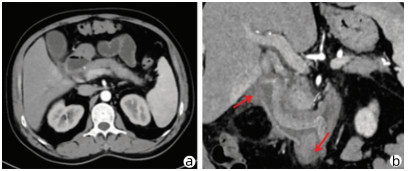

Research advances in peripheral vascular invasion of hepatic alveolar echinococcosis

Han LI, Lizhao HOU

2022, 38(3): 719-723. DOI: 10.3969/j.issn.1001-5256.2022.03.046

Abstract(1150) HTML (294) PDF (1964KB)(43)

Abstract:

Alveolar echinococcosis proliferates in the form of chronic infiltration and has no obvious symptoms and signs in the early stage, and when attending the hospital, some patients already have one or more complications and invasion of important intrahepatic vessels and bile ducts. The research on peripheral vascular invasion of alveolar echinococcosis may help to determine the best individualized treatment and thus improve the cure rate and prognosis of patients. This article reviews the pathological mechanism, clinical manifestations, imaging, clinical classification, and treatment of alveolar echinococcosis.